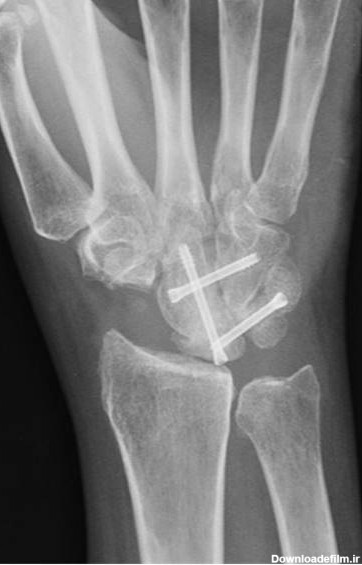

همه چیز درباره رادیولوژی مچ دست. چرا این رادیولوژی تجویز می شود؟ خطرات این تصویربرداری چیست؟ نوبت گیری برای رادیولوژی مچ دست و ...